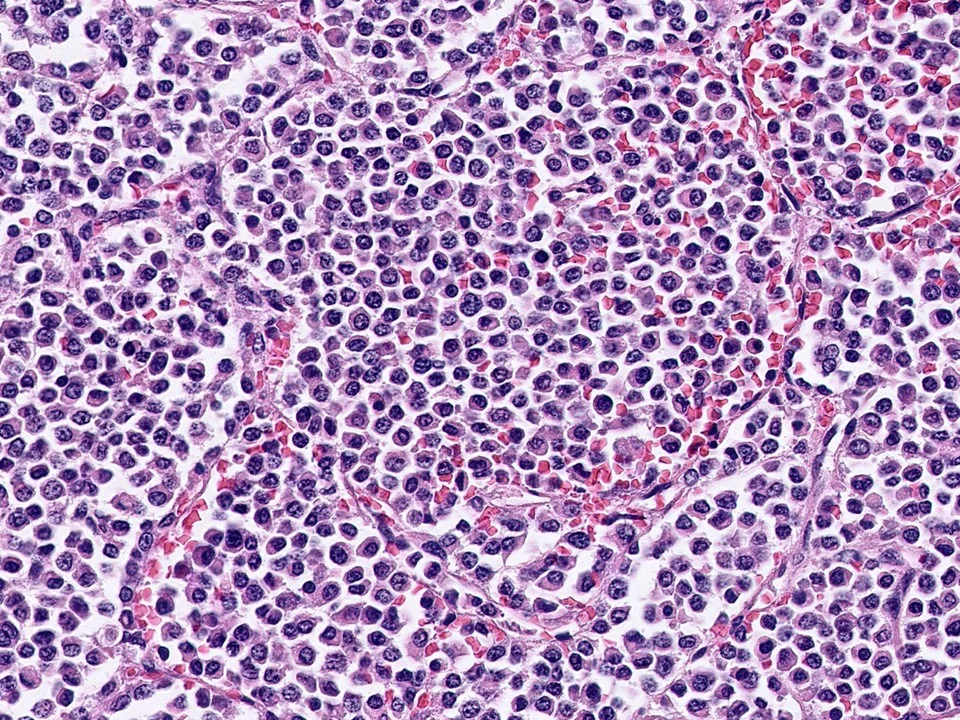

Invasive Lobular Carcinoma, Alveolar Variant

Variant forms of invasive lobular carcinoma differ from the classical form with regard to architectural and/or cytologic features. In the alveolar variant, the cells comprising the tumor are cytologically similar to those of the classical form of ILC. However, they differ with regard to growth pattern.

The alveolar variant of invasive lobular carcinoma is characterized by tumor cells that grow in groups of 20 or more cells that are separate from each other by delicate fibrovascular stroma.

The alveolar variant of invasive lobular carcinoma demonstrates sharply outlined, rounded groups of 20 or more cells that resemble alveoli. They are separated by delicate fibrovascular tissue. They may also have osteoclast giant cells (not pictured).